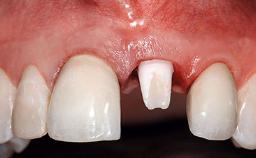

A 32-year-old female Caucasian patient with a compromised maxillary right central incisor was referred to us by a general dentist. Her chief complaints were discomfort and mobility of tooth 11 with unsatisfactory esthetics due to discoloration. The patient reported a previous trauma, some years earlier, as the origin of pathology on the afflicted tooth. Anamnesis was negative for any other dental or periodontal pathology in the remaining dentition. The patient did not take any medication and reported to be a light smoker (5–10 cigs/day). She had high esthetic expectations of her treatment. The extraoral examination revealed a high smile line with full exposure of her maxillary teeth and surrounding soft tissue in the area between the second premolars.

Case Type Single-Tooth Space

Jaw Maxilla

Area Anterior

# of Teeth 1